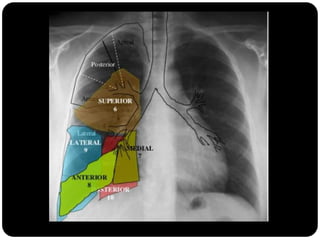

Pulmão direito

Superior: direito

inferior: esquerdo

Vias aéreas

Traquéia       Pulmão direito:

Brônquios           LSD: anterior, apical e posterior;

Bronquíolos

      LM: medial e lateral;

Alvéolos

      LID: superior, basal medial, basal lateral,

basal anterior, basal posterior;

 Pulmão esquerdo:

     LSE: apicoposterior, anterior,

superior(língula), inferior(língula);

     LIE: segmento superior, basal antero-

medial, basal lateral e basal posterior;